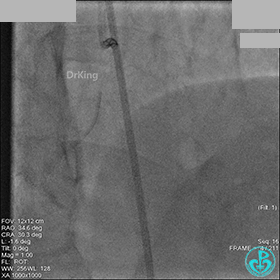

AL 1.0指引导管到位,简单短时尝试导丝不能顺利通过前降支或回旋支病变。改变策略处理右冠脉病变,计划植入2枚支架。AL指引导管到位,Sion blue导丝到达右冠脉远端。导丝通过后1.5mm及2.5mm球囊14~16atm充分扩张中段病变。

右冠脉中段充分扩张后欲植入3.5×38mm支架时,支架难以通过中远段扭曲处,且指引导管、导丝弹出飞扬。反复尝试导丝重新到达右冠脉远端时通过不顺利,局部造影剂滞留,远端血流接近3级。